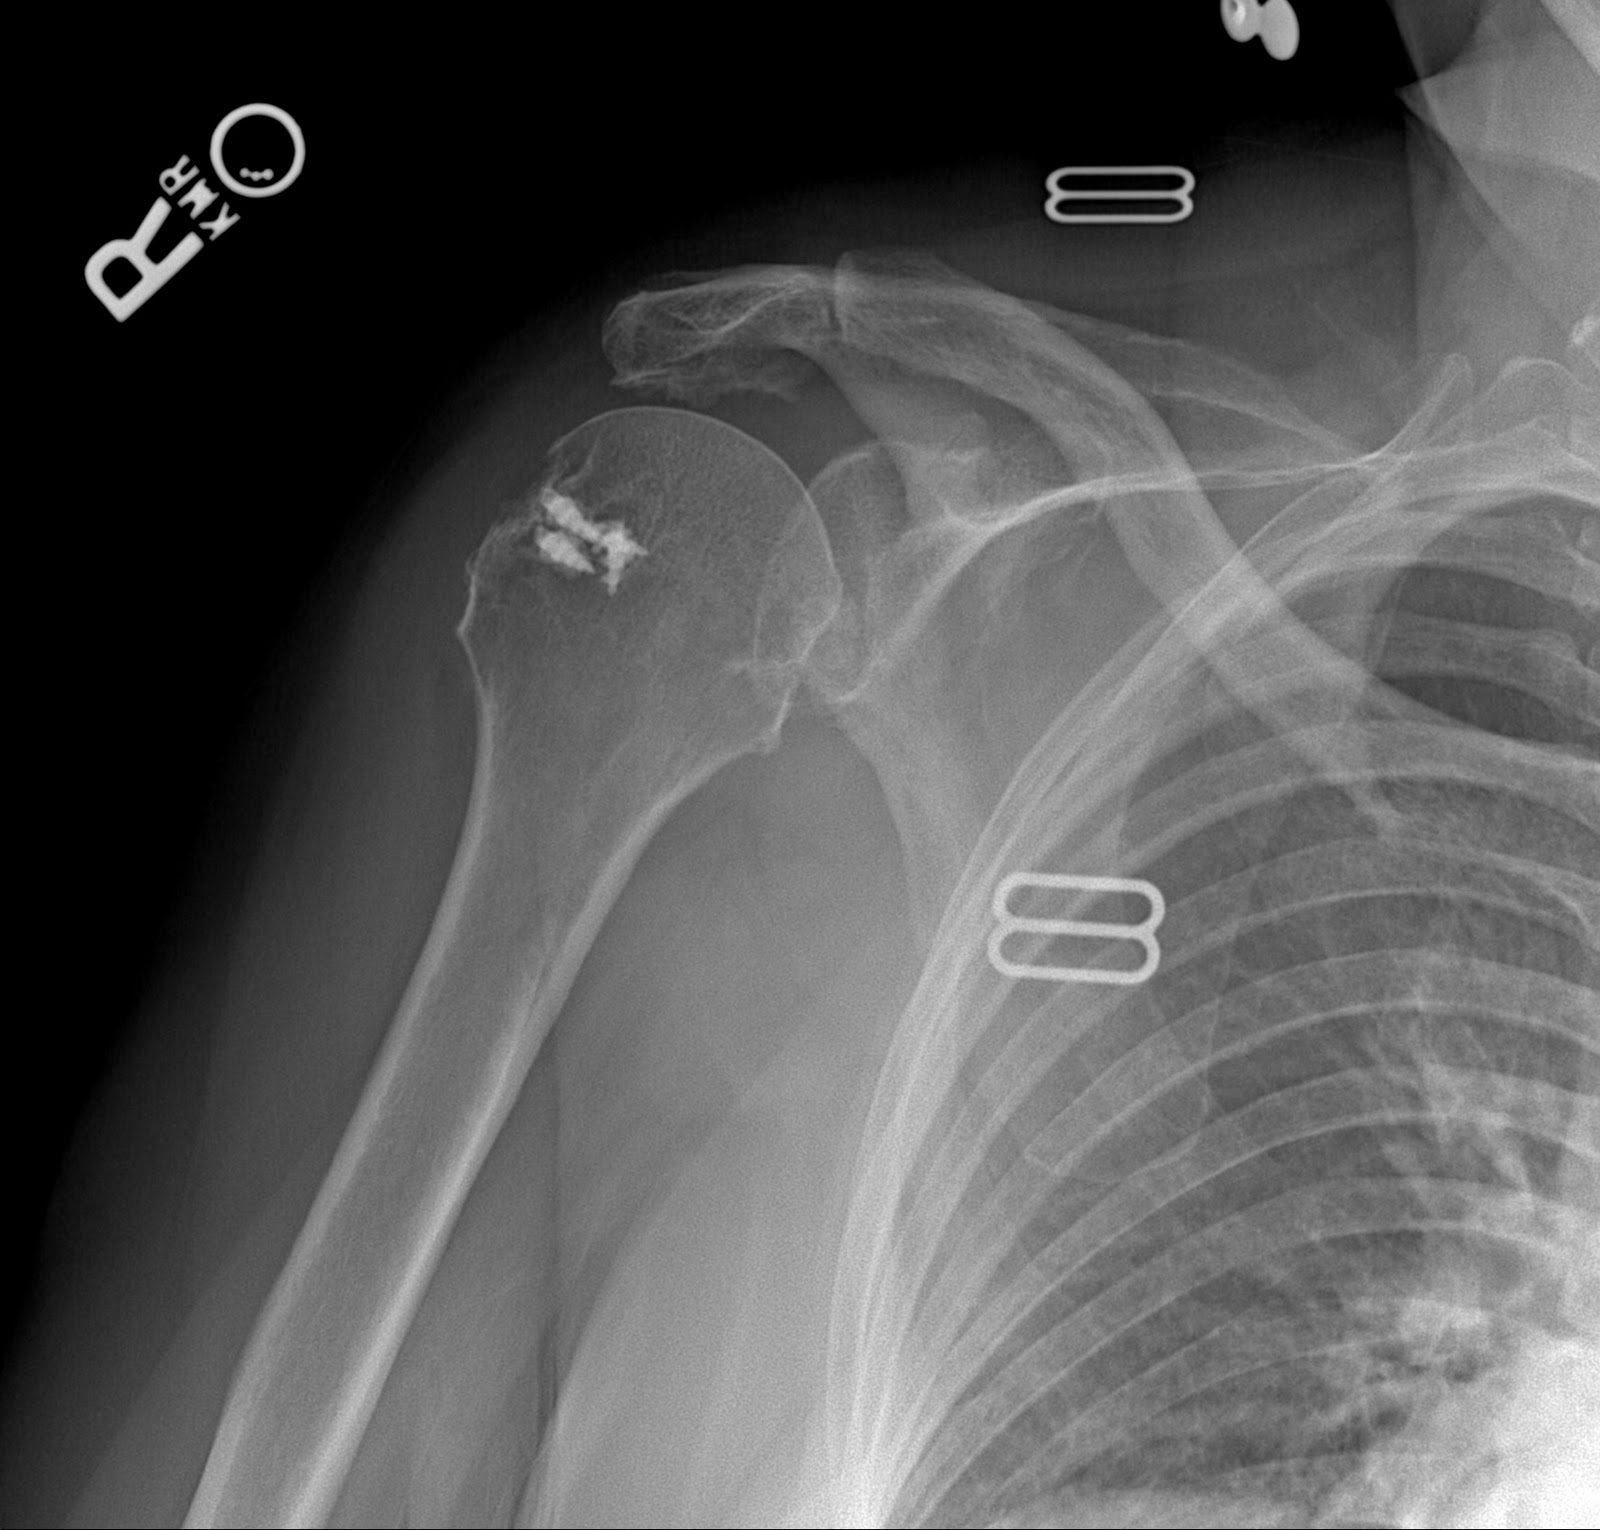

Each patient has had an arthroscopic rotator cuff repair by another surgeon. The first set of films demonstrate that the metal anchors have pulled out of the very soft bone and as a result the tendon has retorn after a rotator cuff repair. This failure was within the first year. This patient was in therapy for many months and could never lift her arm after the repair. Her pain was considerable and she became very unhappy with the situation and eventually came to me for help. A simple x-rays tells the whole story. No MRI needed here. The only set of post operative x-rays done were those done in my office about a year after surgery.

The fact that the anchors are now out of the bone, floating in the joint, indicate that this mechanism of failure. Rotator cuff tendon quality also affects the success of a tendon repair. Poor quality tendon in more likely to retear. Larger tears involving more than one of the 4 rotator cuff tendons will have a higher failure rate as well. Patients over 65 years of age and chronic tendon tears will also have higher rates of failure.

Notice the metal anchors above that seem to be floating in the joint. This foreign body in the joint is very painful. I did surgery on the above patient to remove the anchors arthroscopically. Her pain improved, but her function never recovered. Although I thought she would have done well with a reverse total shoulder replacement, she said that she had enough surgery. I advised her about the limits of surgery under these conditions and, after surgery, she was happy that her pain was improved.